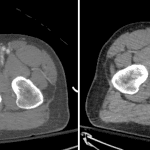

- Small focus of contrast density along the medial aspect of the more posterior right inferior pubic ramus fracture which increases in size on delayed images. Adjacent obturator internus intramuscular hematoma

- Pelvic trauma with arterial hemorrhage

Acute comminuted right sacral fracture and right obturator ring fractures without dislocation or diastasis of the sacroiliac joints or pubic symphysis. Small area of active hemorrhage adjacent to the right inferior pubic ramus fracture with an adjacent obturator internus intramuscular hematoma.